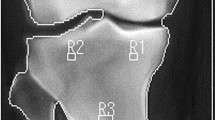

DXA scan image of the knee (a) and heel (b) from one of the study participants. The labeled boxes (R1–R7) delineate the seven RI that were used for the BMD measurements for this participant. The regions in the femur (R1, R2) correspond with the distal femoral metaphysis with the distal edge placed at 15%, and the proximal edge placed at 20% of femur length, as measured from the terminus of the lateral femoral condyle. The width of R1 was set to 70% of the total femur width (measured at the midpoint of the medial and lateral sides of R1), and centered within the bone image. R3 was kept the same size as R1 and centered within the bone image. The proximal edges of R4 and R5 were visually identified and set at two pixels distal to the most distal point of contact visualized between the tibia and fibula. R4 spanned the medial and lateral bone borders and R5 was set to 50% of the bone width (also measured at the midpoint of the medial and lateral sides of R5) and centered within the bone image. (b) Two RIs were used in the calcaneus, including a region (R6) centered within the calcaneus posterior to the calcaneal tuberosity (26 × 12 pixels, 1.32 cm2) with the other encompassing the entire posterior calcaneal body (R7).

Different size regions of interest (RIs) have been used in previous precision analyses of the bones around the knee, including RIs positioned within the visible bone borders,23 whereas others chose regions that spanned the entire bone width.25, 26 Therefore, we assessed the precision of regions at the knee and heel that encompassed the external bone borders (R2, R4 and R7 in Figure 2) as well as regions contained within the visible bone borders (R1, R3, R5 and R6 in Figure 2). The size of each region was specific to each individual, and kept constant between scans. Consistent with earlier protocols23 and to reflect differences in anthropometric measures between participants, the length of all RIs in the femur and tibia was set to 5% of the femur length. In Figure 2a, R1 and R2 correspond to the metaphysis of the distal femur, R3 to the proximal tibia epiphysis and R4 and R5 to the tibia metaphysis. For all scans, any automatically placed extraneous bone was manually removed from the interosseous membranes.

Precision studies of the calcaneus in able-bodied participants used either circumscribed RIs within the visible calcaneus bone borders18 or included most of the calcaneus bone.19, 21, 35 We therefore used both a smaller region centered within the calcaneus posterior to the calcaneal tuberosity (R6 in Figure 2b) and one containing the entire posterior calcaneal body (R7 in Figure 2b).